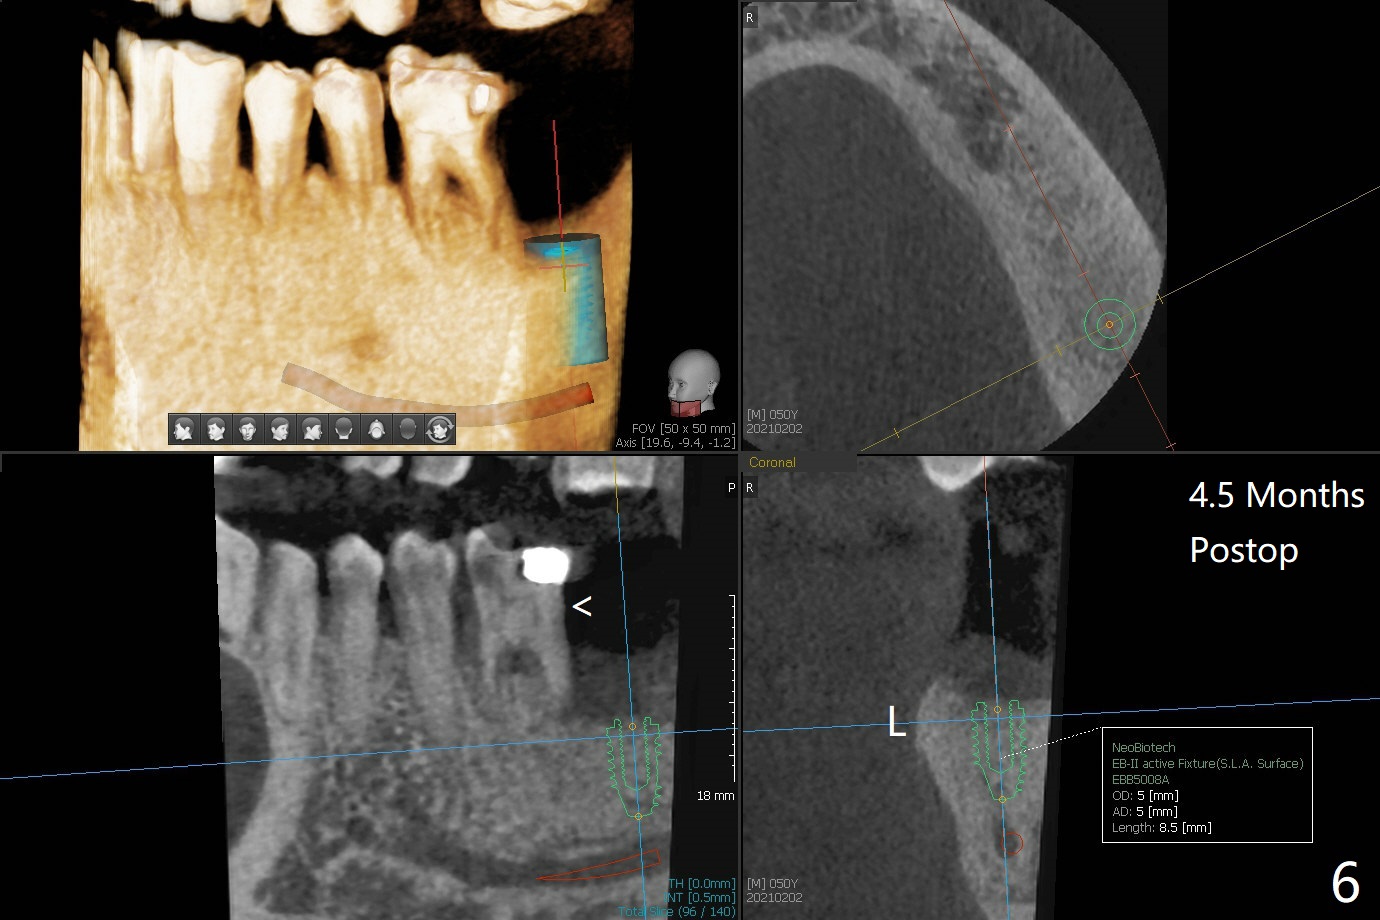

50岁男两年前不肯拔除左下7(图一),现在主动要求治疗(图二),需要做位点保留?怎么做的好?怎么收拾不动脑筋的惨剧(图三:仅远中牙槽窝植骨)?其实需要掀开近中粘骨膜(图四:箭头),然后植骨(红圆圈)。术后4.5个月近中缺损(图五:*),需要植牙植入很低(图六),离邻牙CEJ(<)很远。因此植体应该植入浅些(图七(CT矢状切面):箭头),离牙龈3毫米。放置袖3毫米(图八:粉红色)基台(紫色),然后在基台和植牙浅部植入粘性骨粉(图九:红圆圈)以及PRF膜(蓝线)。从冠状切面来看,颊侧(图十:B)需要多植骨,植牙前翻瓣(图十一:箭头),放置基台后(图十二),放置骨粉,膜,缝合。No Deviation 14 手术 Xin Wei, DDS, PhD, MS 1st edition 09/22/2020, last revision 03/02/2021